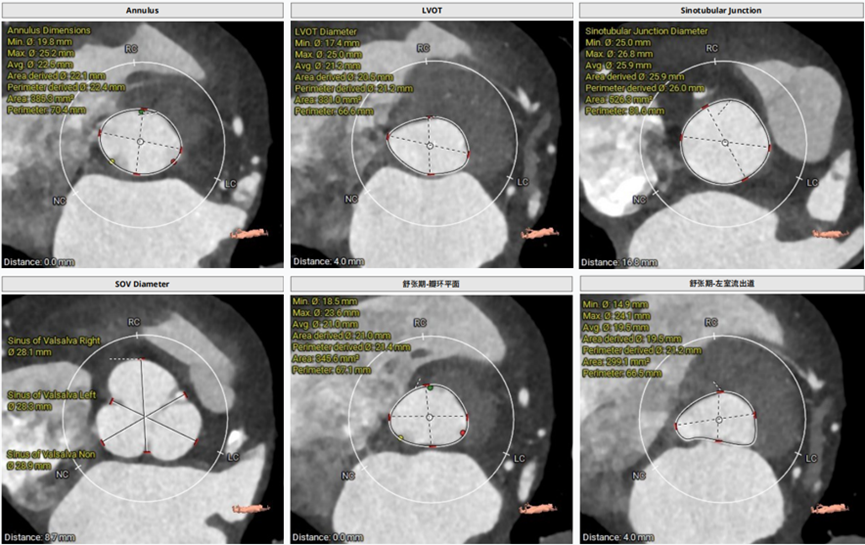

术前CT评估

三叶瓣,主动脉瓣瓣环直径23.3mm,瓣环长短径分别为26.5*20.1mm,周长73.2mm,面积为411.9mm²。左室流出道23.7mm,法式窦33.8mm*30.6mm*31.9mm,左冠高度9.1mm,右冠高度15.7mm,窦管交界 35.1mm,升主动脉直径42.5mm。

瓣环直径:23.3mm;周长:73.2mm

根部解剖情况

LCA 高度9.1mm;RCA 高度15.7mm

瓣上多平面测量

术前CT评估

三叶瓣,主动脉瓣环直径22.4mm;瓣环长短径分别为25.2*19.8mm,周长为70.4mm,面积为385.3mm²。左室流出道21.2mm,法式窦28.3mm*28.1mm*28.9mm;

左冠高度11.7mm,右冠高度13.8mm;窦管交界 26.0mm,升主动脉直径33.3mm。

主动脉瓣瓣环直径22.4mm

根部解剖情况

LCA高度 11.7mm;RCA高度13.8mm